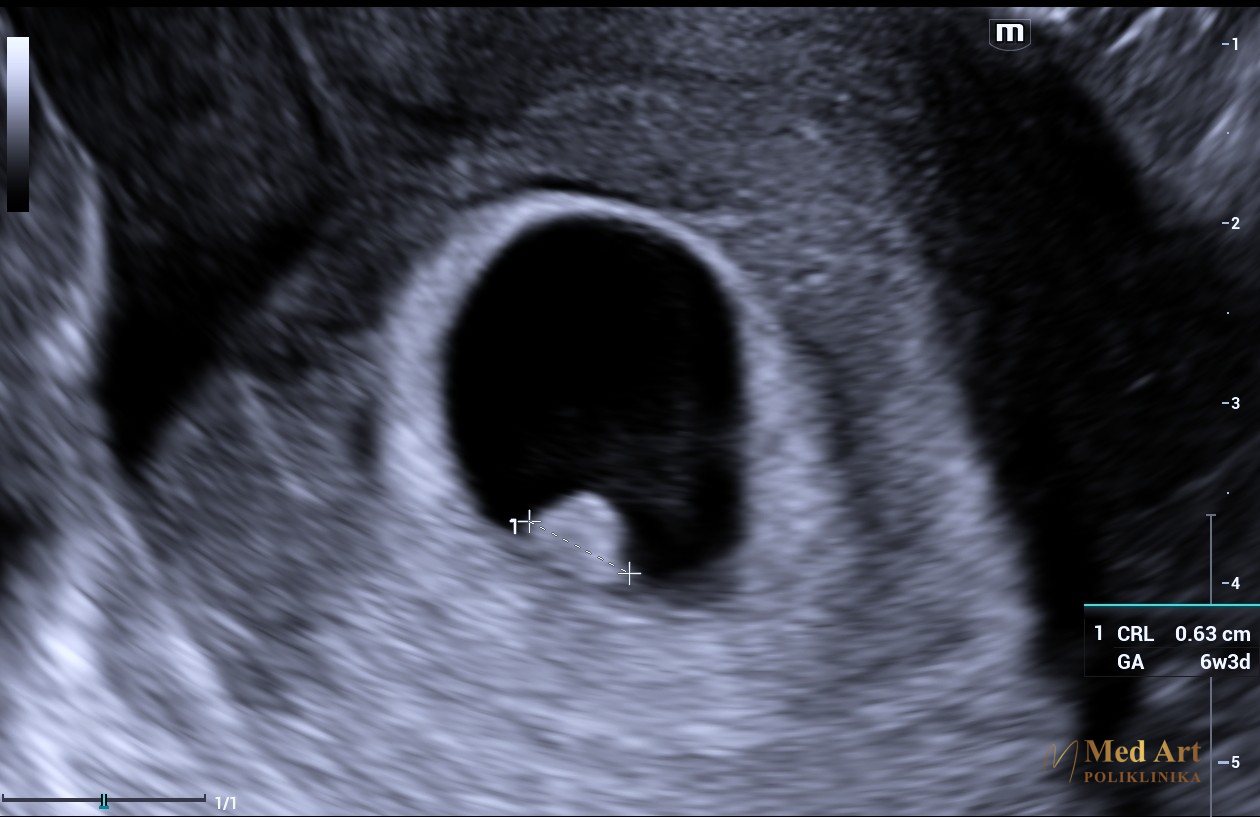

U galeriji koja slijedi, možete vidjeti ultrazvučne slike beba u 6., 7., 8., 12., 14., 20., 21., 24., 27. i 34. tjednu trudnoće, koje prikazuju njihov razvoj od rane trudnoće pa sve do priprema za dolazak na svijet.